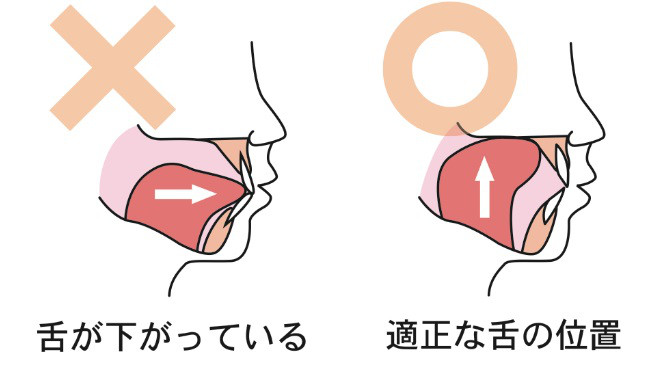

舌癖と舌癖が矯正に及ぼす影響